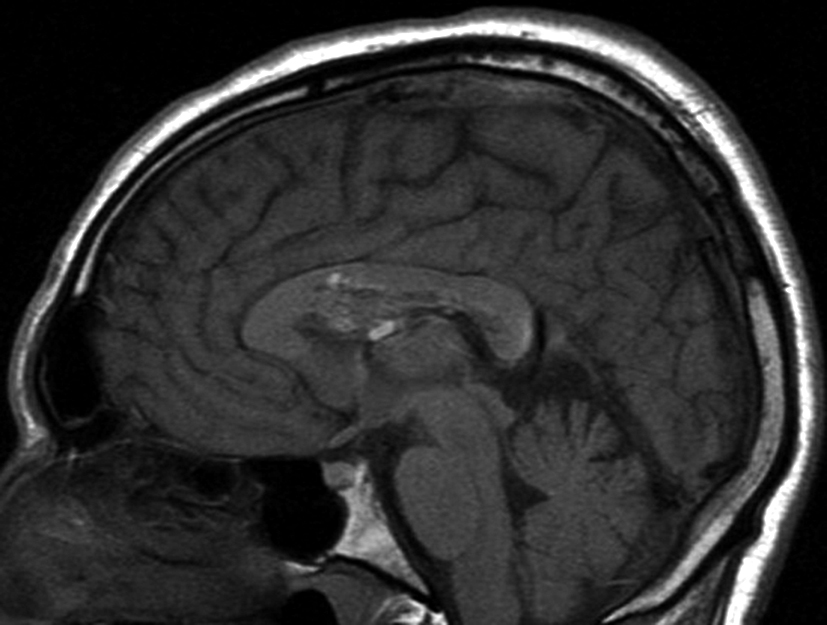

Se presenta el caso clínico de un paciente de sexo masculino, de 36 años de edad, sin antecedentes personales a destacar. Consulta por cefalea holocraneana de larga data, sin déficit neurológico y examen físico normal. Dada la clínica del paciente se realiza una tomografía computada de cráneo sin contraste intravenoso que identifica una lesión bien definida espontáneamente hiperdensa, heterogénea con calcificaciones puntiformes localizada en el asta frontal del ventrículo lateral derecho. No hay edema peri-lesional, efecto de masa ni hidrocefalia (Figura 1- A). Debido a los hallazgos se decide administrar contraste intravenoso, no evidenciándose realce significativo de la lesión (Figura 1- B).

Con los hallazgos tomográficos, no se efectúan planteos diagnósticos y se realiza una resonancia magnética con la finalidad de obtener más datos semiológicos en busca de una aproximación diagnóstica. Se realizó el estudio por medio de secuencias T 1, FSE T 2, FLAIR, SWI y Difusión, en cortes axiales, FSE coronal y sagital T 1. Se realiza la administración de gadolinio DTPA en los tres planos. Se evidencia la lesión bien definida a nivel del ventrículo lateral derecho, que involucra al tronco del cuerpo calloso (Figura 2- C y 3- B). Presenta intensidad de señal heterogénea en secuencias T1 y T2 (Figura 3 y Figura 4). En secuencia ecogradiente se observa una señal marcadamente hipointensa y heterogénea, con un halo hipointenso bien definido (Figura 2- C). No presenta realce significativo tras la administración de Gadolinio (Figura 2- B) y en la secuencia de difusión no presenta restricción.

Figura 2 Resonancia magnética.

a) Imagen axial T1, lesión intraventricular con intensidad de señal heterogénea.

b) Tras la administración de Gadolinio no presenta realce significativo.

c) Imagen axial en secuencia ecogradiente donde se evidencia la lesión hipointensa y heterogénea. Se observa la extensión de la lesión al cuerpo calloso.

a y b) Imágenes sagitales T1, A. se observa la lesión a nivel del asta frontal de ventrículo lateral derecho y B. se evidencia la extensión al cuerpo calloso.